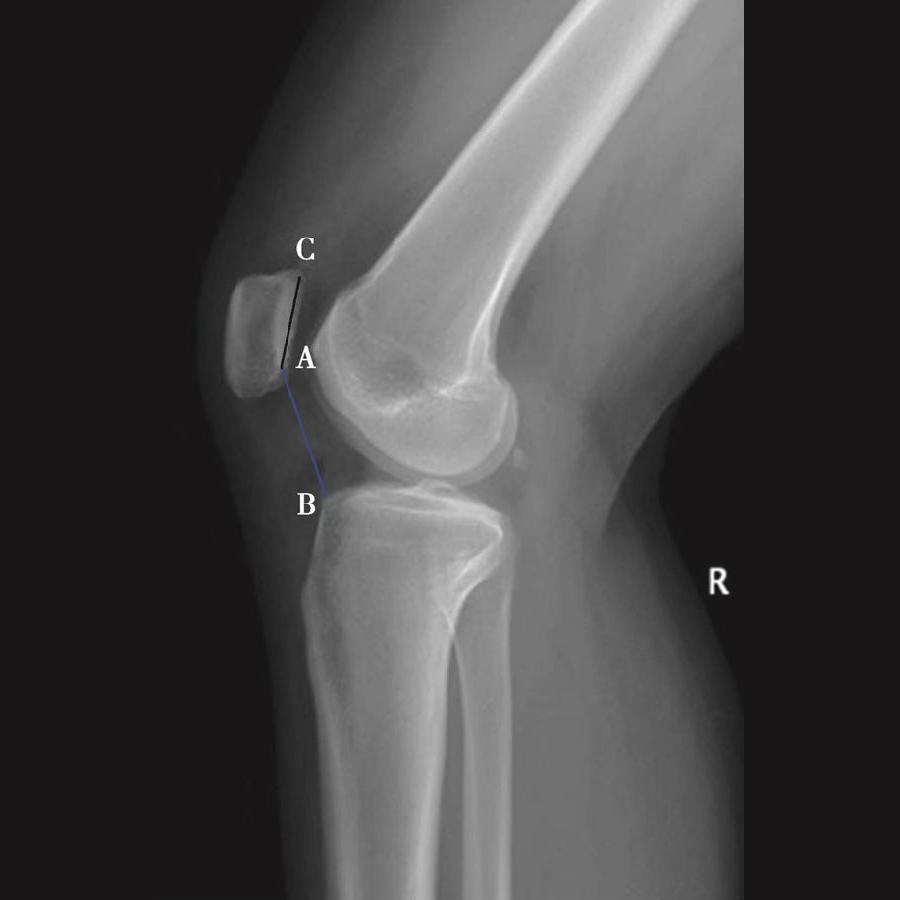

3️⃣ BlackBurne-Peel指数>1.0提示高位髌骨(图8),<0.5提示低位髌骨(图9)。

体位:侧卧位,屈膝无要求。

如图示:AB是髌骨关节面最低点到胫骨平台延长线的垂直距离。AC是髌骨关节面的长度。BlackBurne-Peel指数=AB/AC(图7)。

该方法同样可以评估胫骨结节移位或胫骨高位截骨术后的髌骨高度。但是也有其缺点:①部分患者的髌骨形态异常,难以分辨髌骨关节面的长度;②标记胫骨平台的延长线也需要较高的精度;③胫骨平台后倾角越大,可能导致髌骨关节面的最低点到胫骨平台的延长线的垂直距离越短。因此,如果手术改变了胫骨平台的后倾角度,则会使BlackBurne-Peel指数出现偏差。

图7 BlackBurne-Peel指数=AB/AC=0.80,为正常髌骨高度

图8 BlackBurne-Peel指数=AB/AC=1.20,为高位髌骨